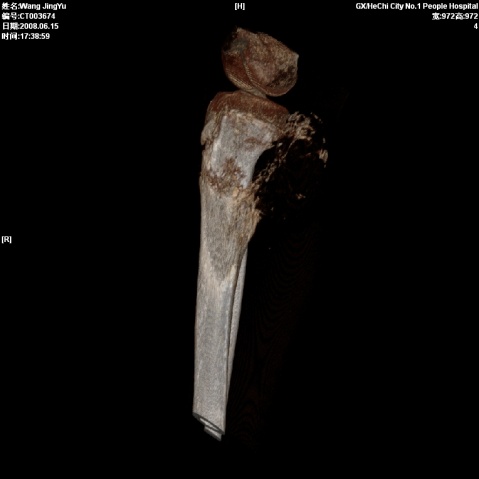

以下是引用随光逐影在2008-6-23 15:30:00的发言:[br]胫骨中上段骨肉瘤(临床表现:好发年龄+好发部位。ct表现:骨质破坏+肿瘤新生骨+骨膜反应并破坏,形成codman氏三角+软组织肿块)。